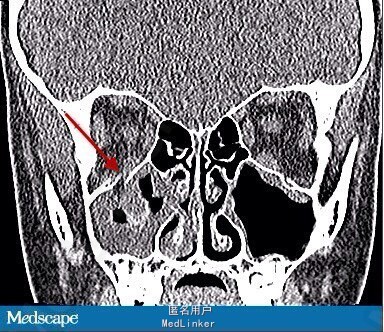

眼部检查:患者近视力1.0,无视野缺损。第一眼位如图1所示。右眼上视有-4的眼球上转不足,下视有-2的下转不足。左眼运动正常。双眼水平运动正常。右眼第一眼位时眼压为13mmHg,上视时眼压增加至23mmHg。左眼眼压为12mmHg。瞳孔正常,双眼附属器以及前后节正常。眼球无震颤。颌面部CT显示右眼眶底轻微骨折。

根据检查结果,诊断为眼眶活板门样骨折致下直肌嵌顿。儿童尤其容易发生此型骨折。儿童骨质相对具有弹性,骨折后会产生反弹,使覆盖于上方的肌肉或者相邻的 组织嵌入骨折缝。这种肌肉嵌顿可以导致特征性的眼球运动障碍。本例患者恶心呕吐的症状提示眼心反射的可能性。